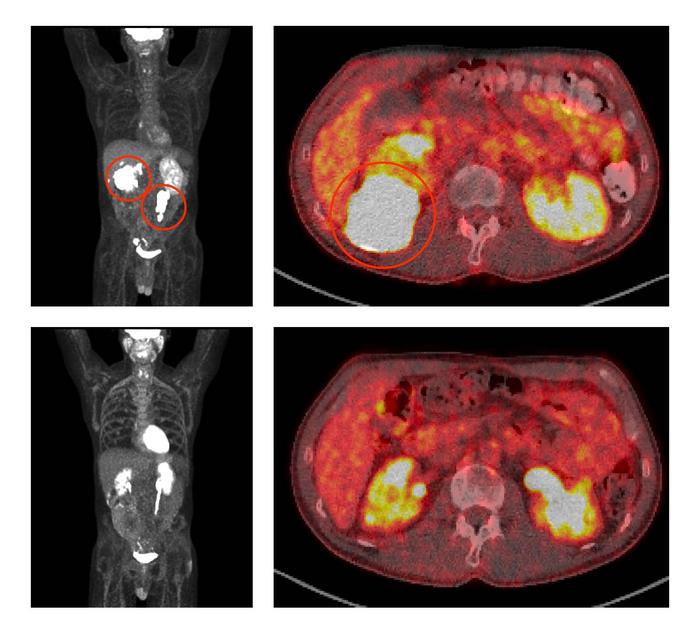

Before treatment with ViPOR, full-body and cross-sectional PET scans of a patient show large lymphoma tumors (circled in the top two panels). Following treatment, the tumors have disappeared (bottom two panels).

Center for Cancer Research/National Cancer Institute